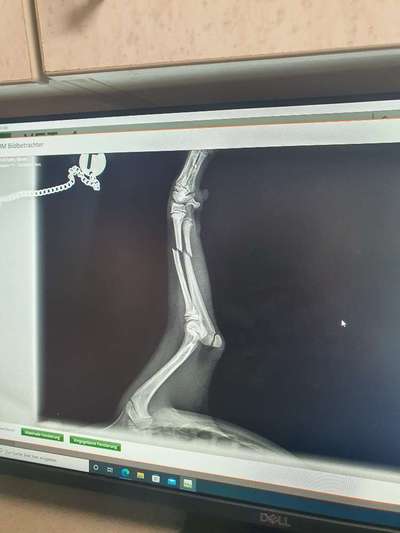

Hallo... Ich habe eine Frage. Hat jemand Erfahrungen mit einem Beinbruch bei einem Welpen? Unser Mailo 16 Wochen alt, hat sich gestern Abend Elle und Speiche gebrochen 😭😭 er ist unglücklich gestürzt....und ich habe immer sooo aufgepasst und alles Welpensicher gemacht aber 1 Sekunde hat gereicht. Er hat jetzt heute morgen eine Platte bekommen...ich wäre dankbar wenn jemand Erfahrung hätte und mir was über die Heilung usw aus Erfahrung berichten kann und vielleicht auch was es so ca gekostet hat. Er soll jetzt noch einige Tage dort bleiben und ich habe Angst das er vielleicht den Bezug zu uns verliert. Er lebt erst 4 Wochen bei uns....danke schonmal.

Anhand des Röntgenbildes handelt es sich um einen glatten Bruch, relativ weit entfernt von den Gelenken, sodass eine Platte gut positioniert werden kann. Insbesondere bei noch wachsenden Hunden verläuft die Heilung sehr schnell.

Dennoch müsst ihr euren Wirbelwind unbedingt einige Wochen schonen. Der behandelnde Tierarzt/ Chirurg entscheidet über die Dauer der Ruhighaltung, den Verbleib der Platte und den weiteren Therapieverlauf. Es werden sicherlich zahlreiche Verbandswechsel und auch Kontrollröntgen anstehen.